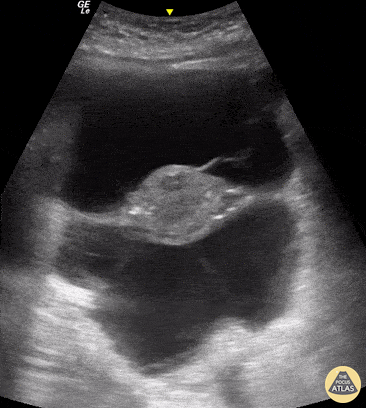

OB/Gyn - TIE Fighter Sign

A 64-year-old woman with hepatic cirrhosis presented to the emergency room with abdominal pain. The abdominal POCUS exam, in this transverse suprapubic view, revealed a large amount of ascites and a floating uterus, an image known as "TIE Fighter Sign" in reference to the famous Star Wars galactic empire ship. Renato Tambelli @R_Tambelli // @JediPocus